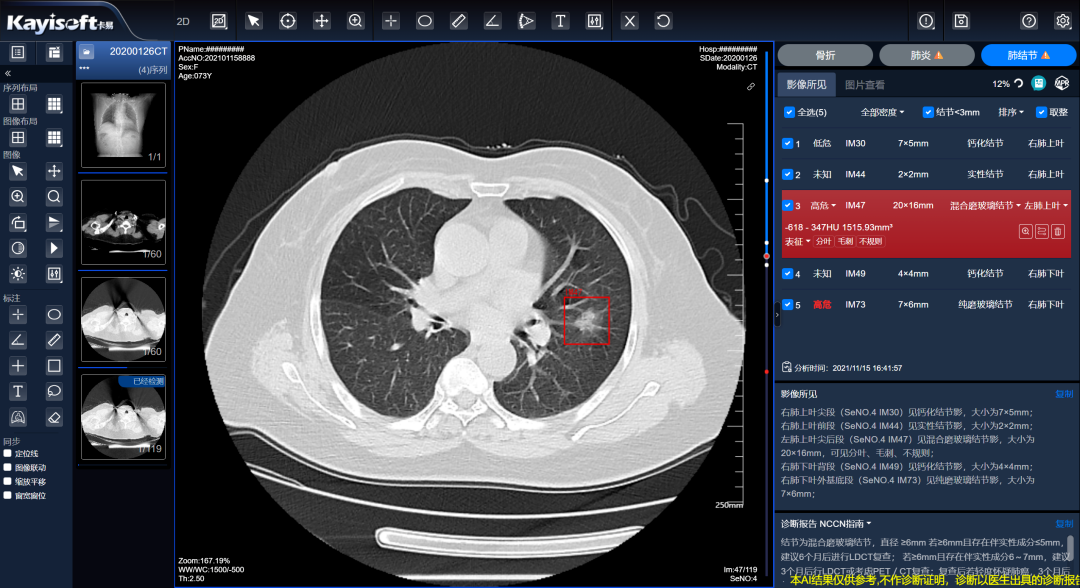

通过全市医学影像云平台完成区域医疗影像数据云化管理数据统一采集,实现以数据为基础,结合 AI 分析服务肺结节智能标注,在短时间内分析完成并生成“AI结构化报告”和“指南参考”来协助诊断医生参考,提高工作效率。

AI分析服务+人的优势组合,其影响不仅仅在于减少重复劳动,提升工作效率,减少因疲劳产生的漏诊现象,更大的作用在于帮助医生职能让渡,合理优化人力资源配置,让医生贴近患者,更加专注于与临床治疗相结合的智慧劳动。

本系统支持与区域的温州市医学影像云平台对接,部署少量的服务器即可满足区域AI影像应用及算力要求,减少服务器资源消耗,所有AI结果的数据可进行汇总,为未来AI的动态跟踪和大数据分析提供强有力的基础支撑。

AI分析服务+影像云的优势组合,能够统筹服务器资源,统一维护便于管理;资源分配更加均匀,使得基层医院也能具备大型三甲医院的诊断能力;各医院可通过基于影像云肺结节AI分析服务实时调阅影像,针对全市范围内的肺结节病例进行量化指标的统计分析。